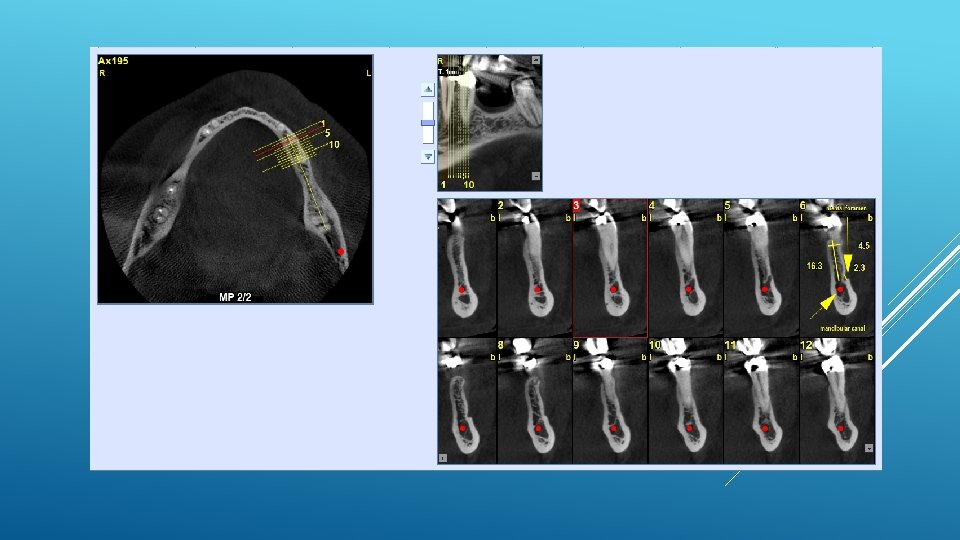

RELATIONSHIP BETWEEN THE POSITION OF THE MENTAL FORAMEN AND THE ANTERIOR LOOP OF THE INFERIOR ALVEOLAR NERVE AS DETERMINED BY CONE BEAM COMPUTED TOMOGRAPHY COMBINED WITH MIMICS The parameters were measured, and their values include mean (SD) anterior loop length, 1. 16 (1. 78) mm; anterior loop angle, 19. 13 (26. 89) degrees; inferior alveolar canal diameter, 3. 01 (0. 67) mm; height of the inferior alveolar canal, 10. 32 (1. 56) mm; 2 -dimensional mental foramen diameter, 2. 97 (0. 61) mm; 3 D mental foramen diameter, 2. 95 (0. 59) mm; 2 -dimensional vertical height of the mental foramen, 14. 67 (1. 67) mm; and 3 D vertical height of the mental foramen, 14. 61 (1. 69) mm. The mental foramen was located apically between the first and second premolars in 51. 67% and below the second premolar in 40. 83% of the cases.